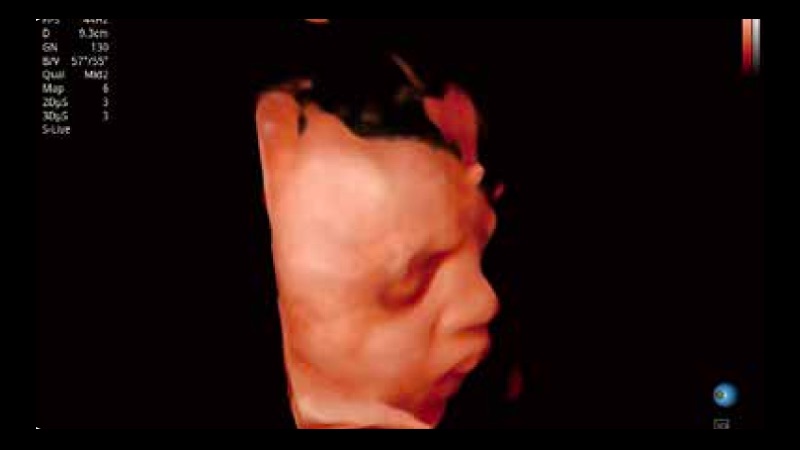

S-Fetus 产科扫查助手

S-Fetus基于大数据深度学习算法,能够帮助您在产前筛查过程中智能识别胎儿标准切面、自动测量并录入报告。一个按键,即可智能、精准、高效地获取胎儿生理指标,极大简化您的产科检查操作。

S-Live 高分辨率容积成像

通过仿真成像技术对3D/4D立体数据进行渲染,多种初始光源位置可选,并支持轨迹球360°光源位置自由调节,清晰显示不同方位容积图像细节。